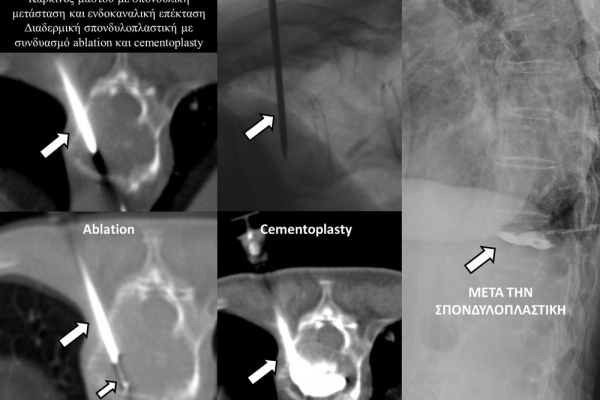

Η τεχνική της διαδερμικής σπονδυλοπλαστικής αφορά την απεικονιστικά καθοδηγούμενη, διαδερμική τοποθέτηση βελόνας εντός του σπονδυλικού σώματος και την υπό συνεχή ακτινοσκοπικό έλεγχο ενδοσπονδυλική έγχυση ακτινοσκιερού, πολυμερούς τσιμέντου (cementoplasty). Oι ενδείξεις της μεθόδου περιλαμβάνουν οστεοπορωτικά και τραυματικά κατάγματα, σπονδυλικές μεταστάσεις, πολλαπλούν μυέλωμα και λέμφωμα.

Ο στόχος της τεχνικής είναι η μείωση του άλγους και η σταθεροποίηση της σπονδυλικής στήλης και επιτυγχάνεται αφ’ ενός με την σταθεροποίηση του σπονδυλικού σώματος και αφ’ ετέρου, επί ογκολογικού υποστρώματος, με την εξώθερμη αντίδραση του πολυμερούς τσιμέντου, η οποία προκαλεί την τοπική καταστροφή του όγκου. Η μέθοδος συνδυάζεται άριστα με την χημειοθεραπεία και την ακτινοθεραπεία και δρα συνεργικά με αυτές.